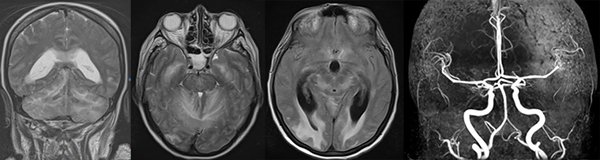

La RMN realizada de inmediato mostró edema cerebeloso y ausencia de compromiso troncal (Figura 8).

Figura 8: RMN y angioRMN: se aprecia edema cerebeloso bilateral, compromiso cerebral a nivel occipital a predominio derecho, balonización del tercer ventrículo y ausencia de oclusiones arteriales.

La evacuación de LCR dio tiempo para colocar una derivación ventricular externa en quirófano, la que se retiró a los 10 días, luego de normalizada la presión del LCR y de corroborar tomográficamente la recuperación del acueducto y del cuarto ventrículo. La paciente, sin embargo, presentó nuevas intercurrencias, tanto a nivel pulmonar como cerebral: hemorragia occipital derecha (Figura 9).

Finalmente, y luego de 45 días de la PTO inicial, logró derivarse a un centro de rehabilitación. Una RMN de control a los 3 meses mostró secuelas menores a nivel parenquimatoso y ausencia de hidrocefalia (Figura 10). A 8 meses del episodio inicial la paciente es independiente, refiere trastornos mínimos en la memoria anterógrada, y deambula por sus propios medios. Al examen neurológico se constata hemianopsia homónima derecha (Figura 11).

Figura 10: izquierda y centro, RMN de encéfalo control realizada a los 4 meses del episodio de hidrocefalia aguda. Se aprecia la secuela del sangrado a nivel occipital derecho: hipointensidad por hemosiderina y retracción del sector ventricular adyacente. Derecha: secuencia T1 sagital donde se aprecia la normalidad de las estructuras infratentoriales.